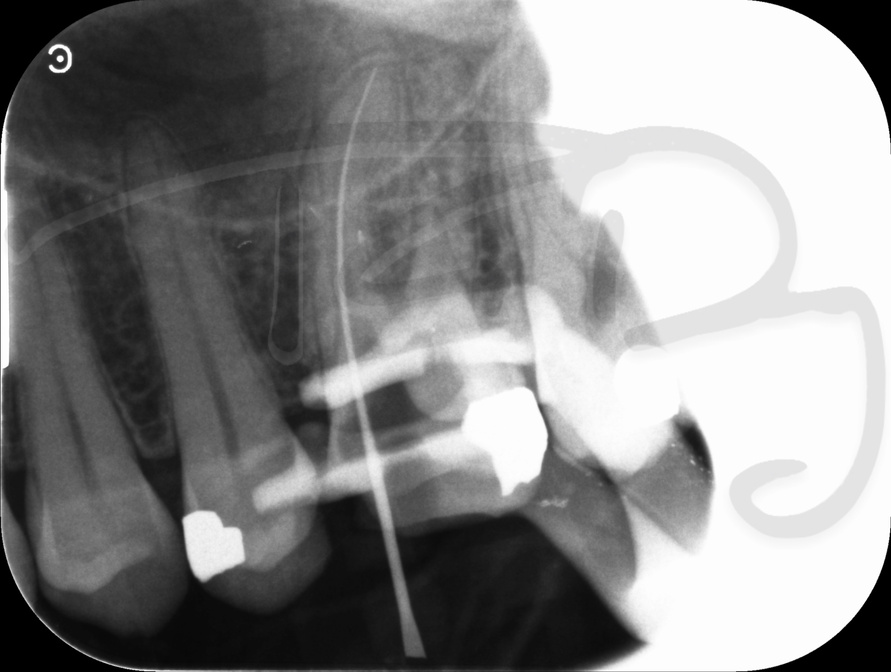

I am pleased to take endodontic referrals. Curved canals >30 degrees and potentially greater than 50 degrees can be negotiated. Sclerosed canals accessed. Post spaces prepared and the patient returned to you ready to restore.In most cases existing crowns, bridges and veneers can be retained with the endodontic access aesthetically restored after the full canal network has been treated.In the first instance I would prefer a radiograph and a brief list of patient expectations and a tooth history.

There are a number of ways to decide whether you need root canal treatment and the specific x-rays, scans and tests help diagnose your problem.An important sign is the type of pain you have been having with a tooth. It helps me decide if a tooth is in need of treatment and even if it saveable.

At the 2017 BDA Conference, Thomas spoke at two lectures about getting the best out of endodontic techniques and equipment.One of the main matters that he covered was understanding the causes of false positive and false negatives in the use of electronic apex locators.He described getting the best out of other methods of root canal length determination available.